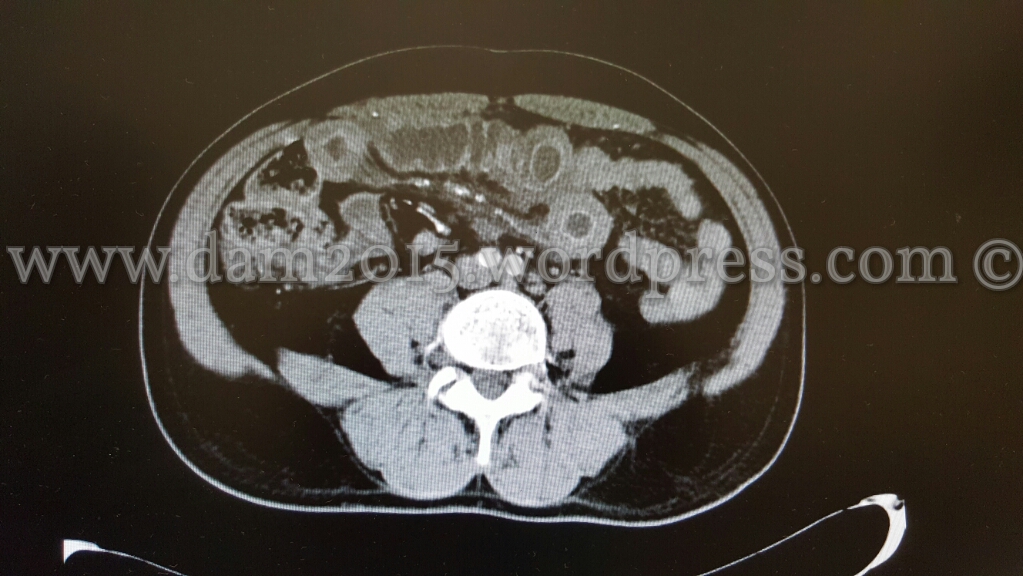

Eseguita TC addome che mostra ispessimento di alcune anse ideali in sede meso-ipogastrica ed in fossa iliaca destra come per infarcimento ematico.

Dopo MDC si osserva iperemia della mucosa a livello delle anse descritte e ridotta rappresentazione della vascolarizzazione del relativo mesentere, che presenta segni di imbibizione edemigena.

I reperti descritti sono suggestivi per quadro di infarto venoso intestinale.